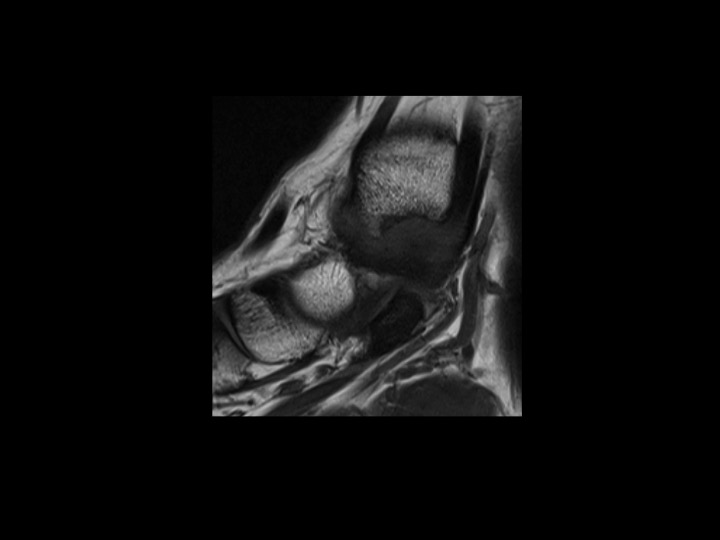

28M basketball injury 6mos ago with pain and tenderness in region of tibialis anterior at anteromedial ankle

This is an uncommon form of ankle impingement characterized by osteophytic spurring at the anterior medial malleolus and adjacent capsular/synovial proliferation and inflammation. The red arrow shows both in slide 1. There is a superimposed partial tear of the posterior (but not anterior) tibiotalar (deep deltoid) ligament, which is separate from this lesion. (note the normal tibialis anterior in slide 1) Reference article.

anteromedial ankle impingement